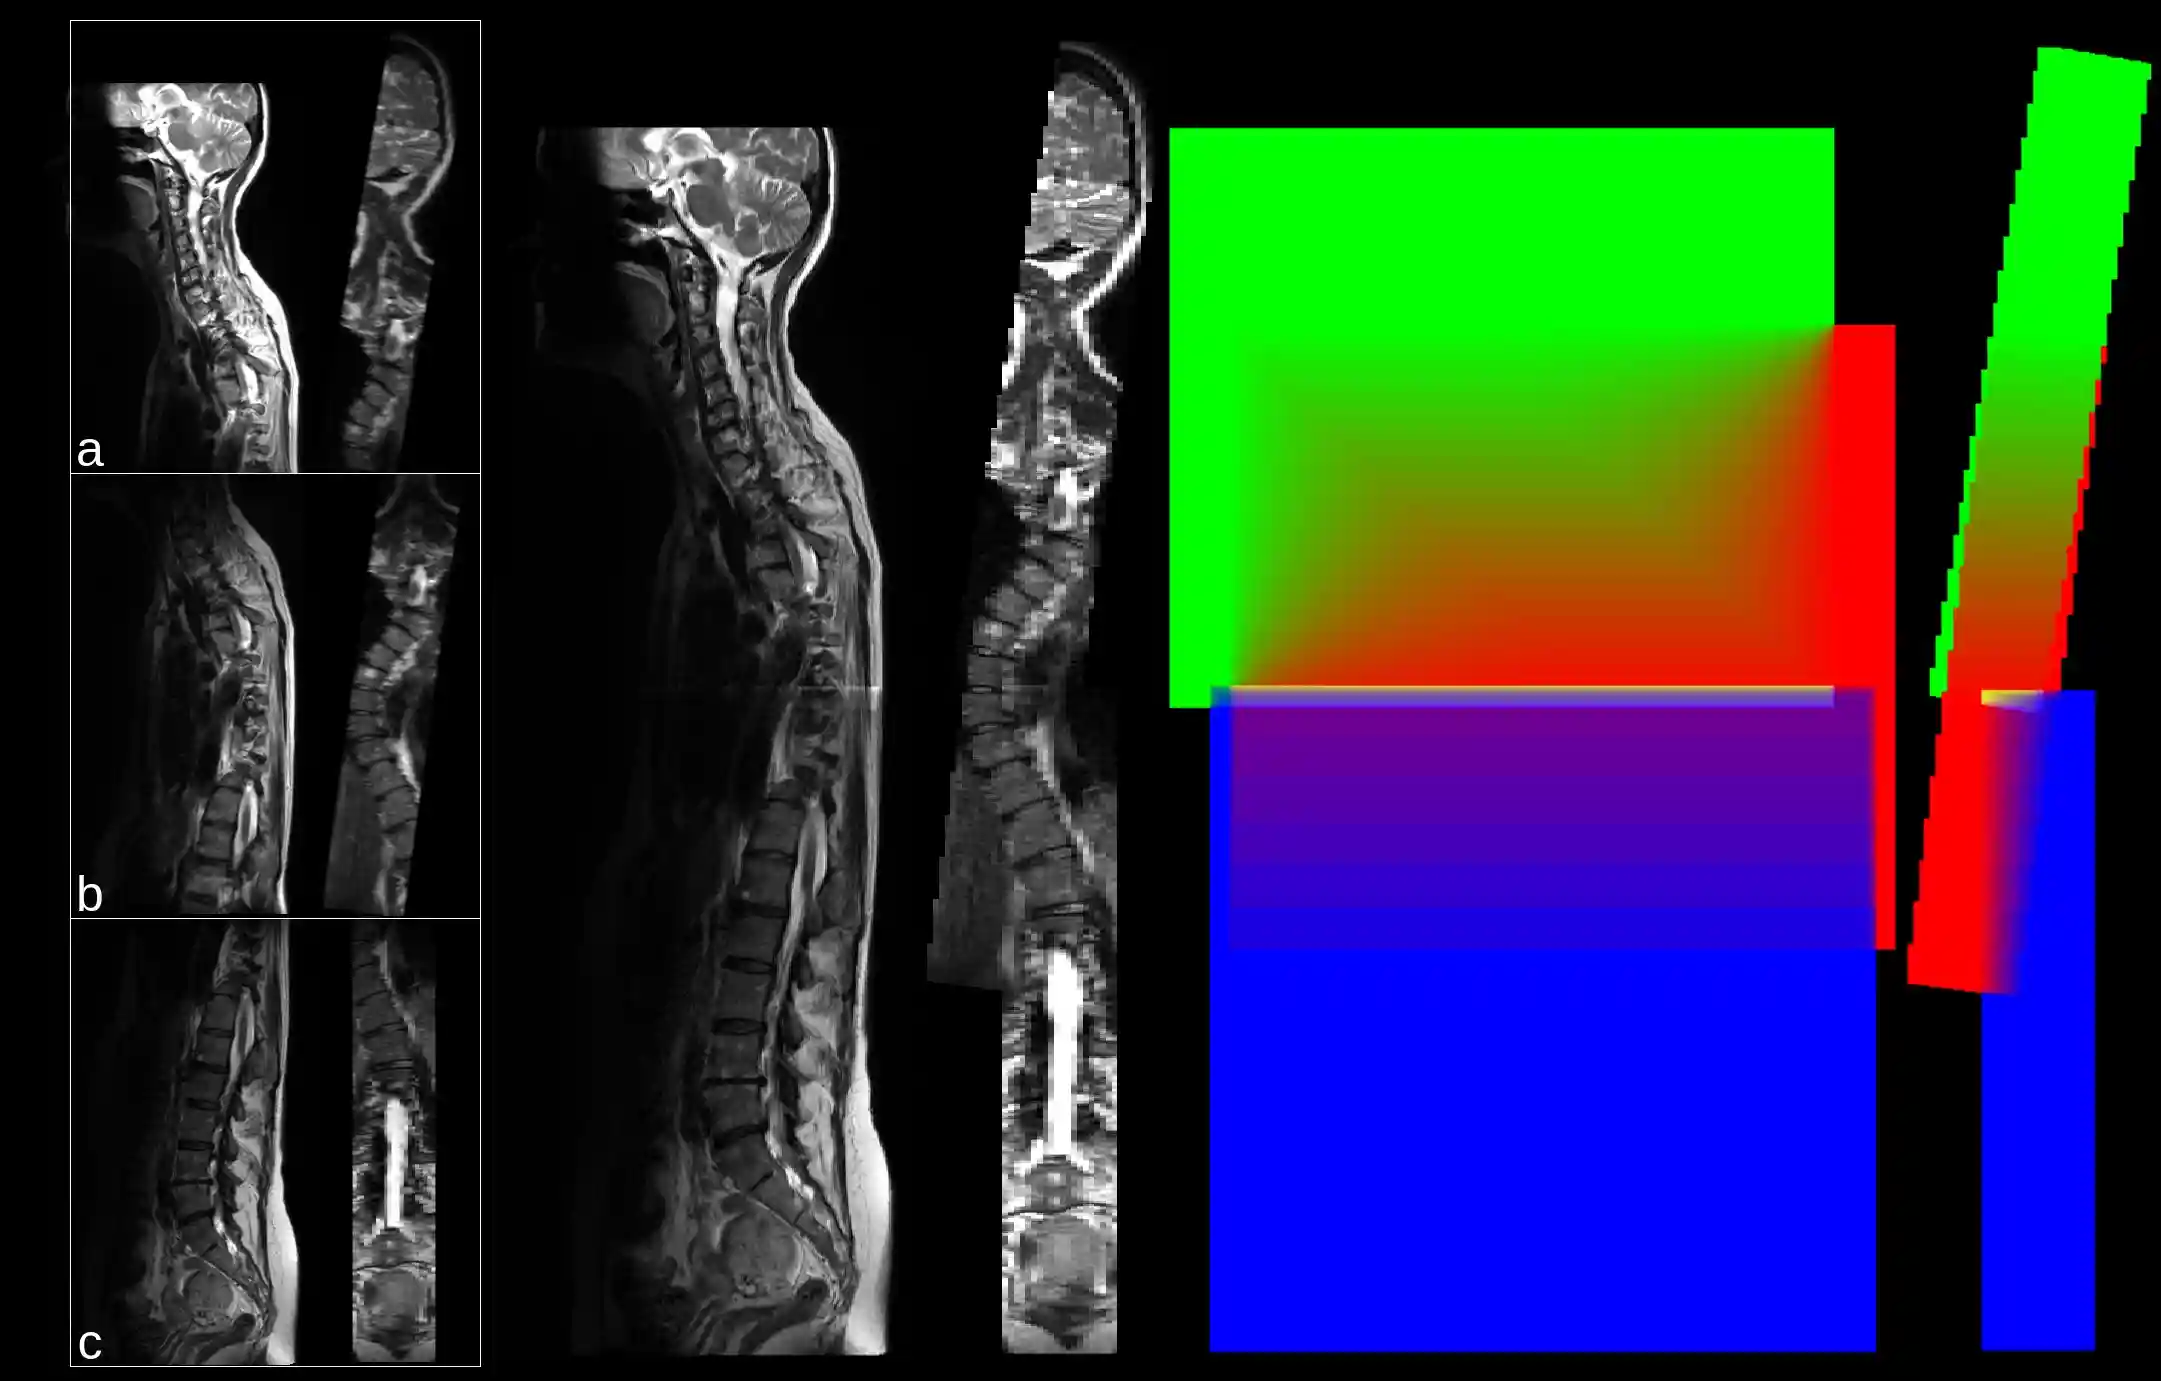

Stitching

Python function and script for arbitrary image stitching. See Details